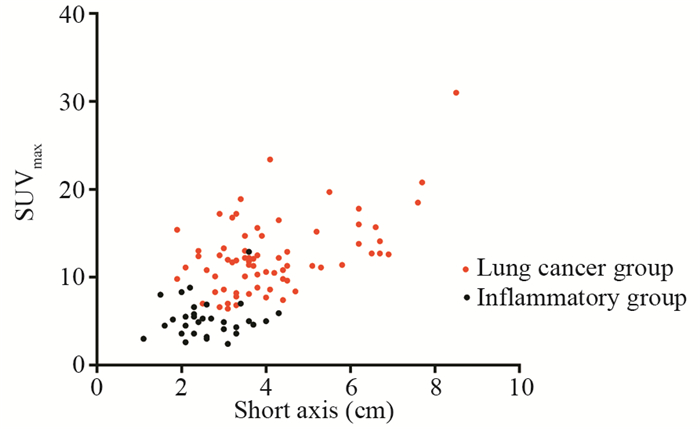

肺癌组SUVmax为6.4~31.0,炎性病变组SUVmax为2.6~12.9,肺癌组高于炎性组,差异有统计学意义((12.46±4.23)vs.(5.26±2.17), P<0.001),但两者有很大重叠。肺癌组短径d为1.9~8.5 cm,炎性病变组短径d为1.1~4.3 cm,肺癌组大于炎性组,差异有统计学意义((4.12±1.46)vs.(2.63±0.76), P<0.001),见图 1。

肺癌组P/D>1者占91.5%(65/71),炎性病变组P/D<1者占80.6%(25/31),两组差异有统计学意义(P<0.001)。以P/D>1为标准,对肺癌诊断的敏感度为91.5%,特异性为80.6%,准确性88.2%,见表 1,图 2~3。

本组病例均为高代谢病灶(所有病例均SUVmax>2.5,良性组平均SUVmax(5.26±2.17),恶性组平均SUVmax(12.46±4.23))。半定量测定显示恶性组以FDG在病灶近心端浓聚为主,良性组以FDG在远心端浓聚为主,以P/D>1为标准,对肺癌诊断有较高的敏感度(91.5%)、特异性(80.6%)和准确性(88.2%)。